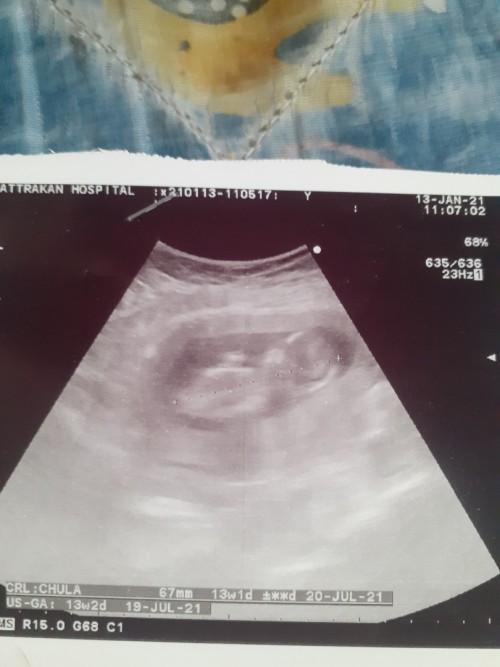

ตอน13+2